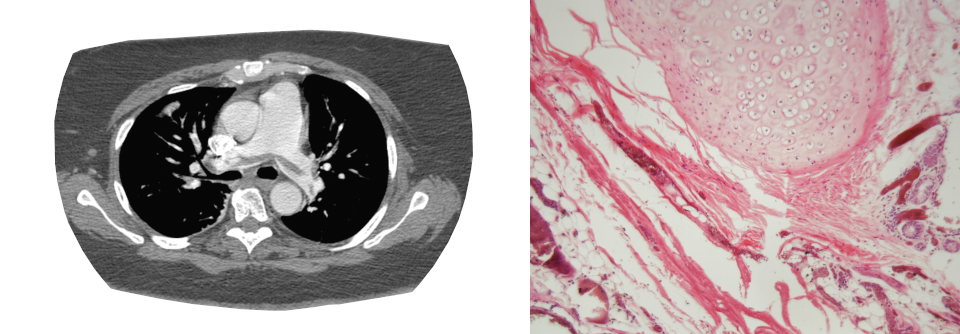

Lungenembolie in der linken Lunge. Lungenembolie in der linken Lunge. © wikipedia/James Heilman, MD (CC BY-SA 4.0)

Lungenembolie mit Nachweis eines großen Thrombus innerhalb der rechten Pulmonalarterie. Lungenembolie mit Nachweis eines großen Thrombus innerhalb der rechten Pulmonalarterie. © wikipedia/Bernd Brägelmann Braegel (CC BY-SA 3.0)